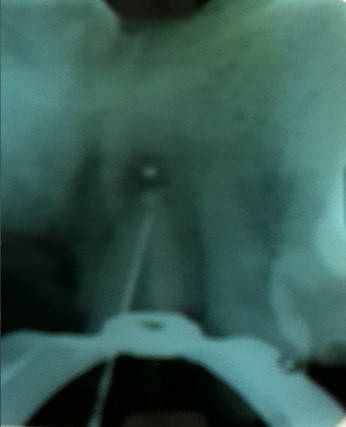

No caso relatado neste trabalho, o atendimento foi realizado no paciente que procurou a clínica da Universidade Tuiuti do Paraná. Por meio de exame intraoral, observou-se a presença de fístula na mucosa vestibular do dente 11, o que ficou comprovado por meio do rastreamento de fístula com cone de guta-percha e posterior exame radiográfico. Este revelou a presença de tratamento endodôntico insatisfatório e lesão periapical do paciente, que procurou a clínica de Odontologia da Universidade Tuiuti do Paraná, pois não ouve sucesso no tratamento endodôntico convencional feito anteriormente feito na própria clínica.

Ao exame radiográfico, observou-se extensa área radiolúcidas, constatando uma fístula, lesão periapical envolvendo região periapical do referido dente.

- Figura 2 – Radiografia periapical do ápice com a presença de fístula.

- Figura 3 – Radiografia periapical do retratamento endodôntico.